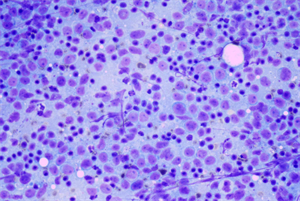

近日,明慧工程师了解到一家宠物医院需要用到显微镜摄像头搭配奥林巴斯显微镜观察宠物肿瘤的需求,为其推荐了MHD2000高清相机的显微成像系统。这一推荐满足了客户的实验需求,在现场演示过程中因清晰的成像效果得到客户的充分肯定和认可。

1.高分辨率成像:MHD2000高清摄像头能够清晰的捕捉到肿瘤的微小细节,肿瘤组织形态、细胞特征清晰可见,借助相机配备的MingHui 1.0显微软件,不仅能快速拍摄、清晰记录成像画面,更能为宠物肿瘤的病理分析、病情确诊提供客观、详细的图像依据,助力医护人员制定精准诊疗方案,有效提升宠物诊疗效果与生命周期。

明慧MHD2000高清相机与奥林巴斯显微镜的高效适配,为研究宠物肿瘤提供了可靠的平台。其提供的高清、精准的成像数据,有助于实验人员快速获取准确的病理诊断依据,也优化了宠物肿瘤诊疗的实验条件,为提升宠物存活率提供了有力保障。